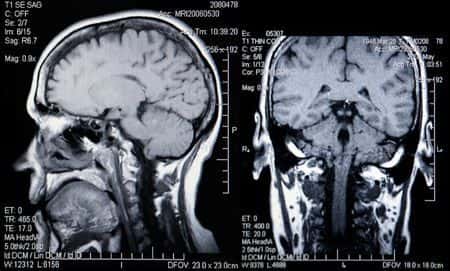

This case involves a generally healthy and active forty-five-year old male with a history of multiple sclerosis. The patient experienced a syncopal episode overnight while attempting to urinate. As a result, the patient fell and sustained a blow to the back of the head, losing consciousness. The patient’s wife called their primary care physician to see if she should bring him to the emergency room and the doctor said that it was fine to just observe him closely. Over the next few days, the patient complained of headaches and extreme nausea. The patient was sent for an MRI that indicated a suspicious spot indicative of an aneurysm in the region of the anterior communicating artery, but no further testing or follow-up was conducted. Several months later, the patient was found by his wife on the floor of the bedroom displaying seizure like activity. He was rushed to the ER. The patient was diagnosed with a subarachnoid hemorrhage and was transferred to a tertiary care hospital for emergency surgery. Upon transfer, the patient was then diagnosed with a ruptured anterior communicating artery aneurysm and a micro surgical clipping of the anterior communicating artery with a ventriculostomy was performed. Despite the intervention, the patient remained in a coma for most of the hospitalization. He eventually regained consciousness, but he suffered intractable brain damage, which caused severe paralysis and memory loss. He was transferred from acute rehabilitation to a nursing home, where he remained until his death two years later.